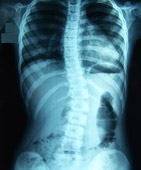

Radiografía de una columna vertebral con escoliosis

Dedicada al restablecimiento del aparato músculo-esquelético y de la postura, centrándose en la columna vertebral y traumatismos.